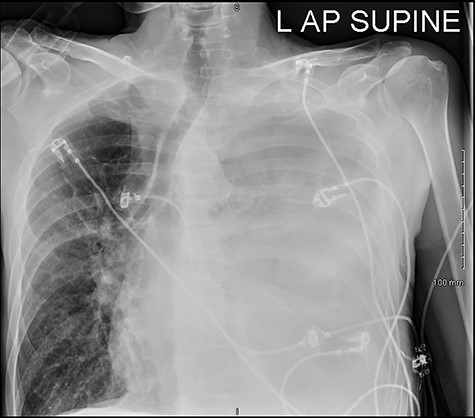

He was readmitted three days post-discharge with worsening pleuritic chest pain and dyspnoea. On admission, he was febrile and tachycardic. On examination, he had absent breath sounds and dullness to percussion over the left mid and lower zones of his chest. Chest x-ray confirmed a large left-sided pleural effusion (Fig. 1), which was consistent with a massive haemopneumothorax on cross-sectional imaging (CT) (Fig. 2). A chest drain was inserted that drained 6 l of serosanguinous fluid. The patient deteriorated thereafter and required inotropic support and empirical broad-spectrum antimicrobials, piperacillin-tazobactam (4.5 g IV) and gentamicin (5 mg/kg IV) in the intensive care unit.